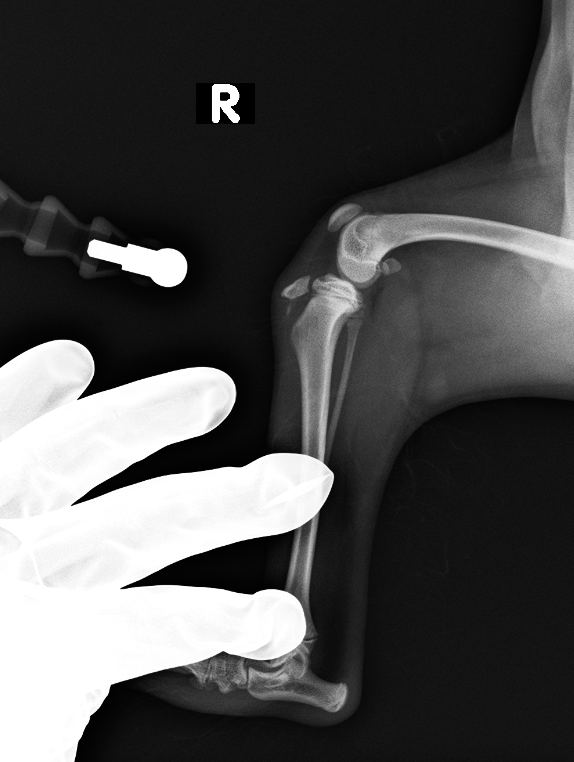

レントゲン検査より、脛骨粗面成長板の剥離

before